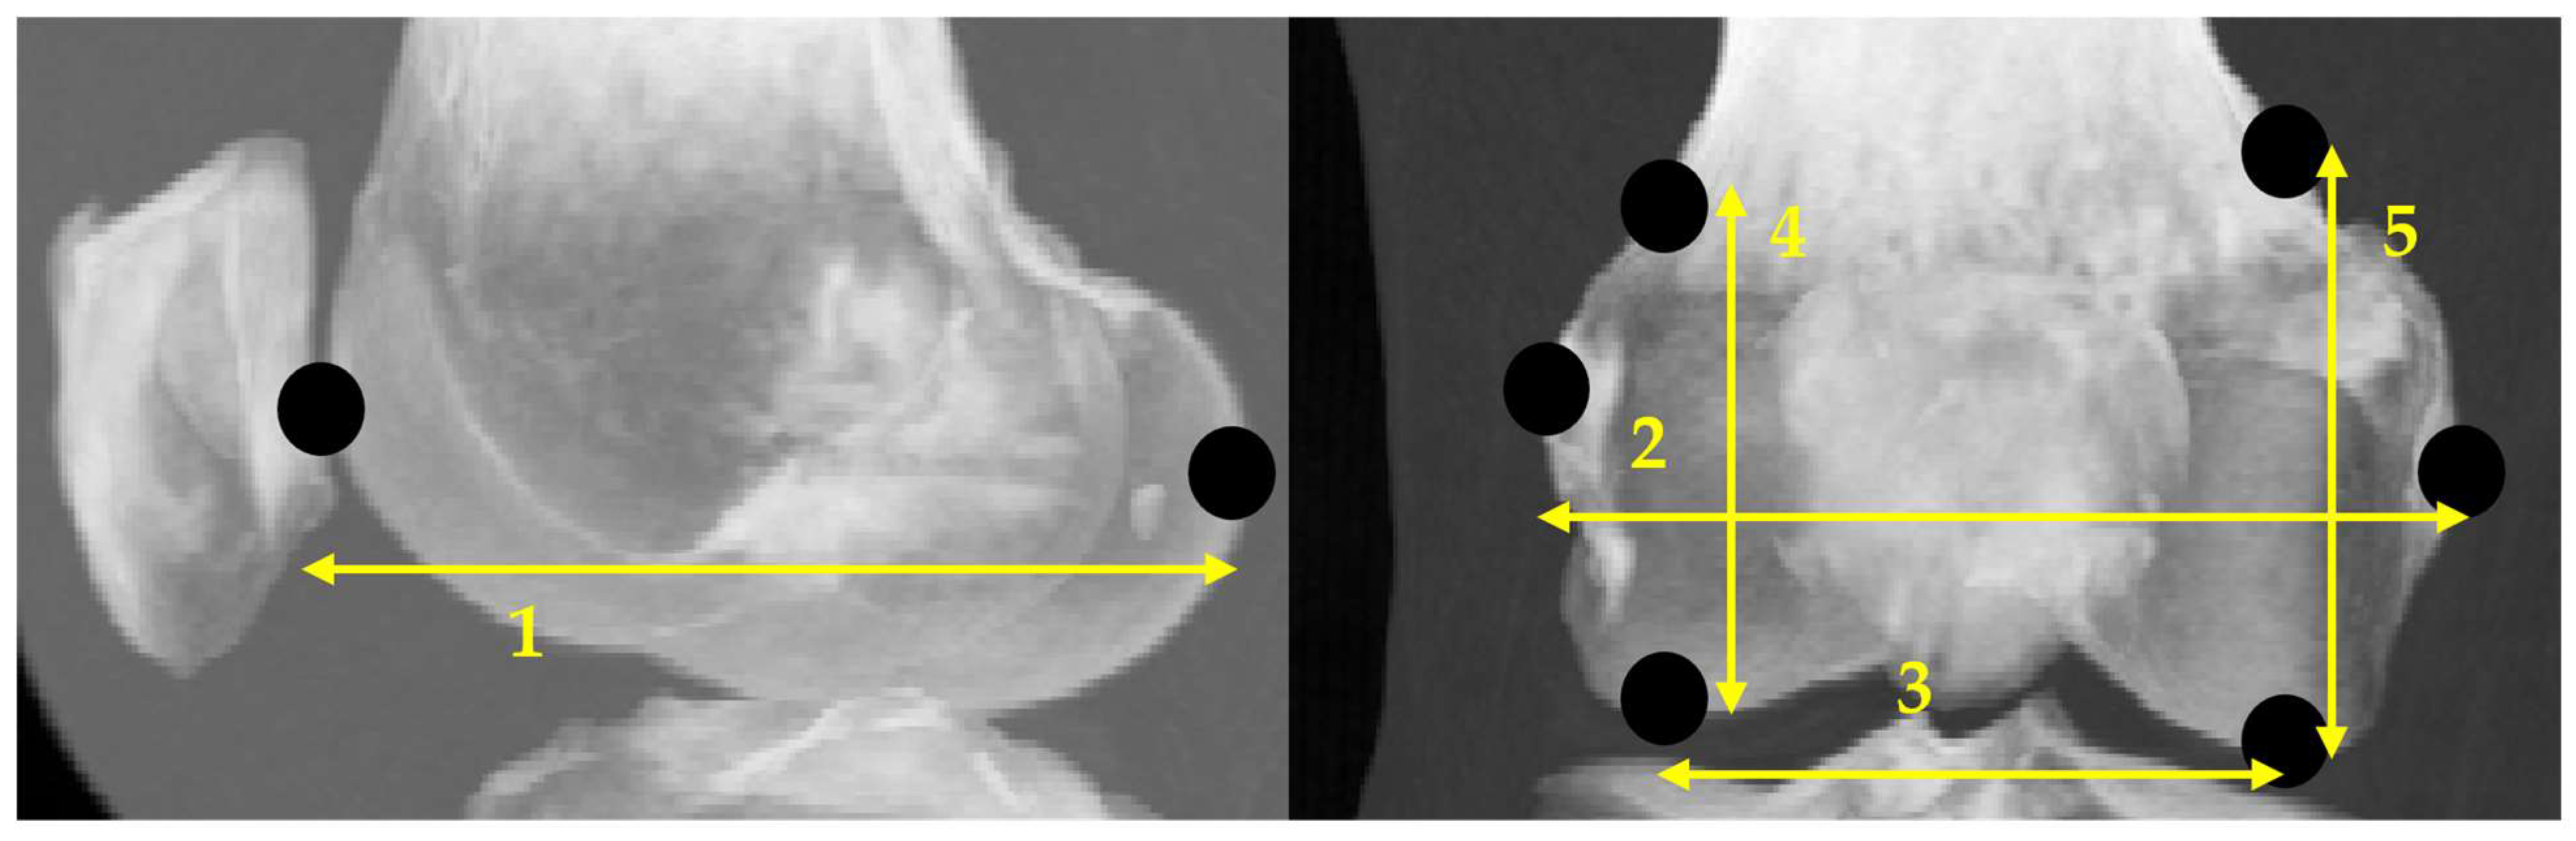

2.3.1. Anatomical Feature Point

2.3.2. Scanning Feature Values

- Select two points located at both ends.

- Of the two points obtained in step 1, designate the point located posteriorly in the sagittal plane and laterally in the coronal plane as the reference point.

- Draw a perpendicular line on the images that divides the two points into n equal parts.

- Obtain the intersection of the line drawn in step 3 and the bone contour line.

- Calculate the distances between all points and the reference point and use them as the feature values.